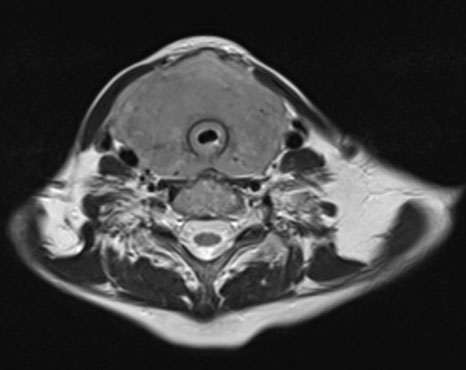

Fourteen years later, the patient presented to our institution with a palpable cervical mass. A total body CT revealed a non-enhancing diffusely enlarged hypodense thyroid gland without the presence of enlarged lymph nodes or other significant abnormalities (Figure 3). A magnetic resonance (MR) examination of the neck done one month later showed a rapid increase in size of the thyroid gland demonstrating diffuse enhancement postgadolinium administration and restricted diffusion. It showed to exert mass effect on the surrounding structures and significant narrowing of the airways. No pathological lymph nodes were seen (Figure 4, Figure 5, Figure 6). Because of the patient’s previous history of lymphoma and rapid growth of the thyroid gland, the possibility of extra-nodal thyroid lymphoma recurrence was raised, and a core needle biopsy of the thyroid gland was done and sent to pathology which confirmed the presence of diffuse large B-cell lymphoma within the thyroid gland.

Figure 5: Axial T2 MR image (2025) showing a diffusely enlarged heterogeneous thyroid gland with mass effect on the surrounding structures and significant narrowing of the airways.